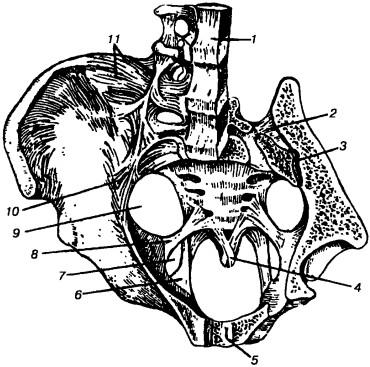

Ábra. 136. ínszalagok és sustvvy medence (RD Sinelnikov). Horizontális és szagittális eltávolítjuk a vágások a bal Innominate csont, bal oldalon a keresztcsont csont- és L, „_, v: 1 - lig. longitudinale anterius, 2 - lig. sacroiliaca interossea, 3 - art. sacroiliaca, 4 - lig. sacrococcygeum ventrale, 5 - symphysis pubica, 6 - lig. sacrotuberale, 7 - foramen ischiadicum mínusz 8 - lig. sacrospinale, 9 - foramen ischiadicum majus 10 - lig. sacroiliaca ventralia, 11 - lig. iliolumbale